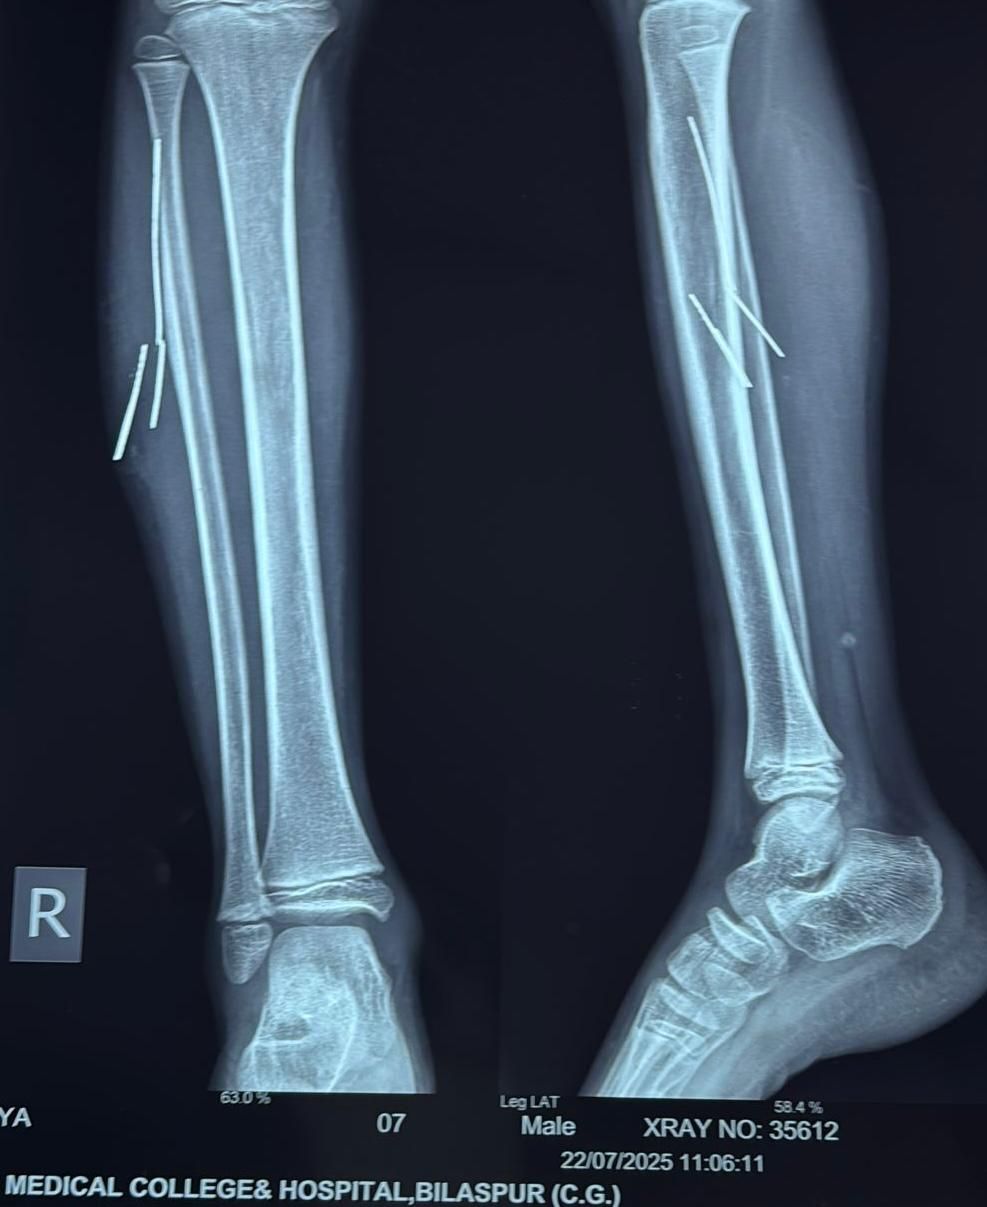

लमेर निवासी 10 वर्षीय आदित्य खांडे पिता दीप कुमार लगभग चार माह पूर्व साइकिल चलाते समय दुर्घटनाग्रस्त हो गया था। हादसे में साइकिल का टायर फटने से बाहर निकला लोहे का तार उसके दाहिने पैर में घुस गया। तार पैर में टूटकर अंदर फंस गया और चार टुकड़ों में लगभग 2 से 5 सेमी लंबाई में मांसपेशियों में धंस गया। इसके बाद बच्चे को लगातार सूजन और दर्द की शिकायत बनी रही।

तीन दिन पूर्व परिजन उसे सिम्स के सर्जरी विभाग में लेकर पहुंचे, जहां सर्जन डॉ. बी.डी. तिवारी ने जाँच करवाई। एक्सरे और सोनोग्राफी से यह पुष्टि हुई कि तार पैर की मांसपेशियों में गहराई तक धंसा हुआ है, और अंदर ही अंदर मवाद बन चुका है।